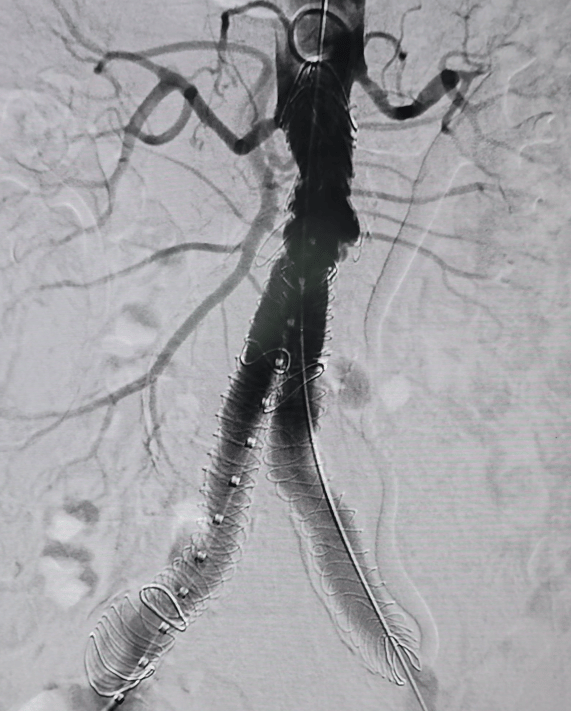

Exclusion de Aneurismas

Los aneurismas son dilataciones anormales de las arterias que debilitan una sección específica, lo que aumenta el riesgo de ruptura.

Existen dos métodos principales para la reparación de aneurismas: la reparación abierta y la reparación endovascular (EVAR).

En la reparación abierta, se accede a la cavidad abdominal para exponer completamente la arteria afectada. Luego, se coloca un injerto sintético en el sitio del aneurisma para restaurar la integridad arterial.

La reparación endovascular (EVAR) sigue el mismo principio de exclusión del aneurisma, pero se realiza a través de pequeñas punciones en las arterias. A través de estas punciones, se introducen catéteres para colocar una prótesis y reforzar la arteria desde el interior.